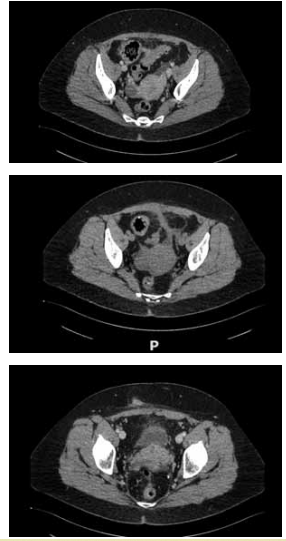

Mulher de 41 anos apresentou quadro de diverticulite aguda perfurada e bloqueada, sendo submetida à laparoscopia com limpeza e drenagem da cavidade. Evoluiu bem no

pós-operatório, com dreno progressivamente menos produtivo e retirado no 10º PO. Retorna 2 meses após a cirurgia, assintomática, afebril, sem dor abdominal, mas com

secreção purulenta diária por orifício cutâneo no local do

dreno, em pequena quantidade, suficiente para sujar uma

gaze por dia. Foi realizada uma tomografia de abdome,

demonstrada nas imagens a seguir:

(Arquivo pessoal; imagem usada com autorização)

Sobre a evolução deste quadro, assinale a alternativa correta.